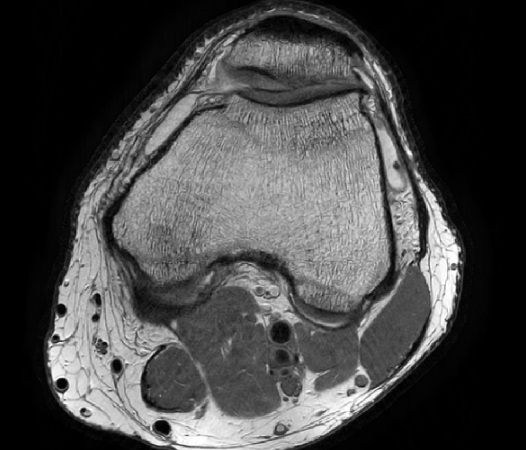

In the example below, only one fifth of the required MR radiofrequency signals is recorded. This results in a five times faster acquisition, with a subsampled k-space (top left) and inherent image artifacts after standard reconstruction (top right).

Philips Compressed SENSE

The Compressed SENSE reconstruction then uses iterative, knowledge-based algorithms to fill in the empty lines in k-space (bottom left). This removes the artifacts while keeping the final image fully consistent with the acquired data (bottom right). *Compared to Philips MR exams without Compressed SENSE